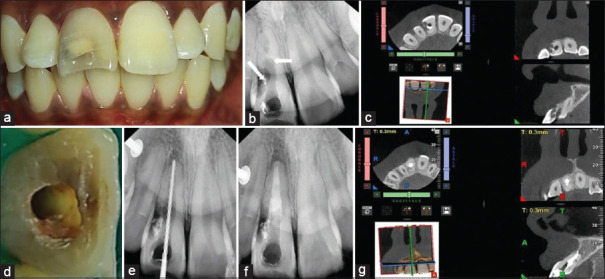

The presence of both a pathologic external cervical resorption (ECR) and an iatrogenic over-enlarged root canal with a widened apex can significantly compromise the structural integrity of a tooth. Furthermore, regular restorative-endodontic management of the involved tooth poses many procedural challenges and difficulties. However, a multi-modal approach involving nonsurgical and surgical procedures with the application of advances in endodontics can help to manage and salvage such a tooth. This article aims to report on a case of multi-modal management with the application of cone-beam computed tomography, micro-endodontics, bioactive and biomimetic materials, and monobloc effect to manage and structurally rehabilitate and reinforce a tooth affected by both ECR and over enlarged canal with a widened apex. This multi-modal approach was applied with nonsurgical and surgical treatments to restoratively and endodontically manage the affected tooth. Clinical and radiographic follow-up of the tooth was uneventful and showed satisfactory and favorable outcomes.